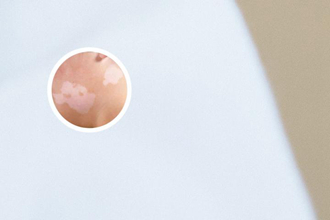

通過(guò)皮膚鏡,我們可以看到白斑的顏色變化,這些變化可以幫助醫(yī)生區(qū)分不同類型的白斑。例如,白癜風(fēng)的白斑通常是乳白色或瓷白色,而其他疾病,比如真菌感染,其白斑的顏色可能偏黃色或褐色,而銀屑病的白斑則可能呈銀白色或淡黃色。

皮膚鏡下,還可以觀察白斑的形狀和邊界,這些特征也是判斷白斑性質(zhì)的重要依據(jù)。白癜風(fēng)的白斑通常呈圓形或橢圓形,邊界清晰,而其他疾病的白斑可能呈不規(guī)則形狀,邊界模糊。

皮膚鏡可以放大觀察白斑的表面結(jié)構(gòu),例如毛囊的分布、鱗屑的形狀、血管的走向等。白癜風(fēng)的表面結(jié)構(gòu)通常是光滑的,沒(méi)有顯然的變化,而其他疾病可能會(huì)出現(xiàn)鱗屑、結(jié)痂、毛囊炎等變化。